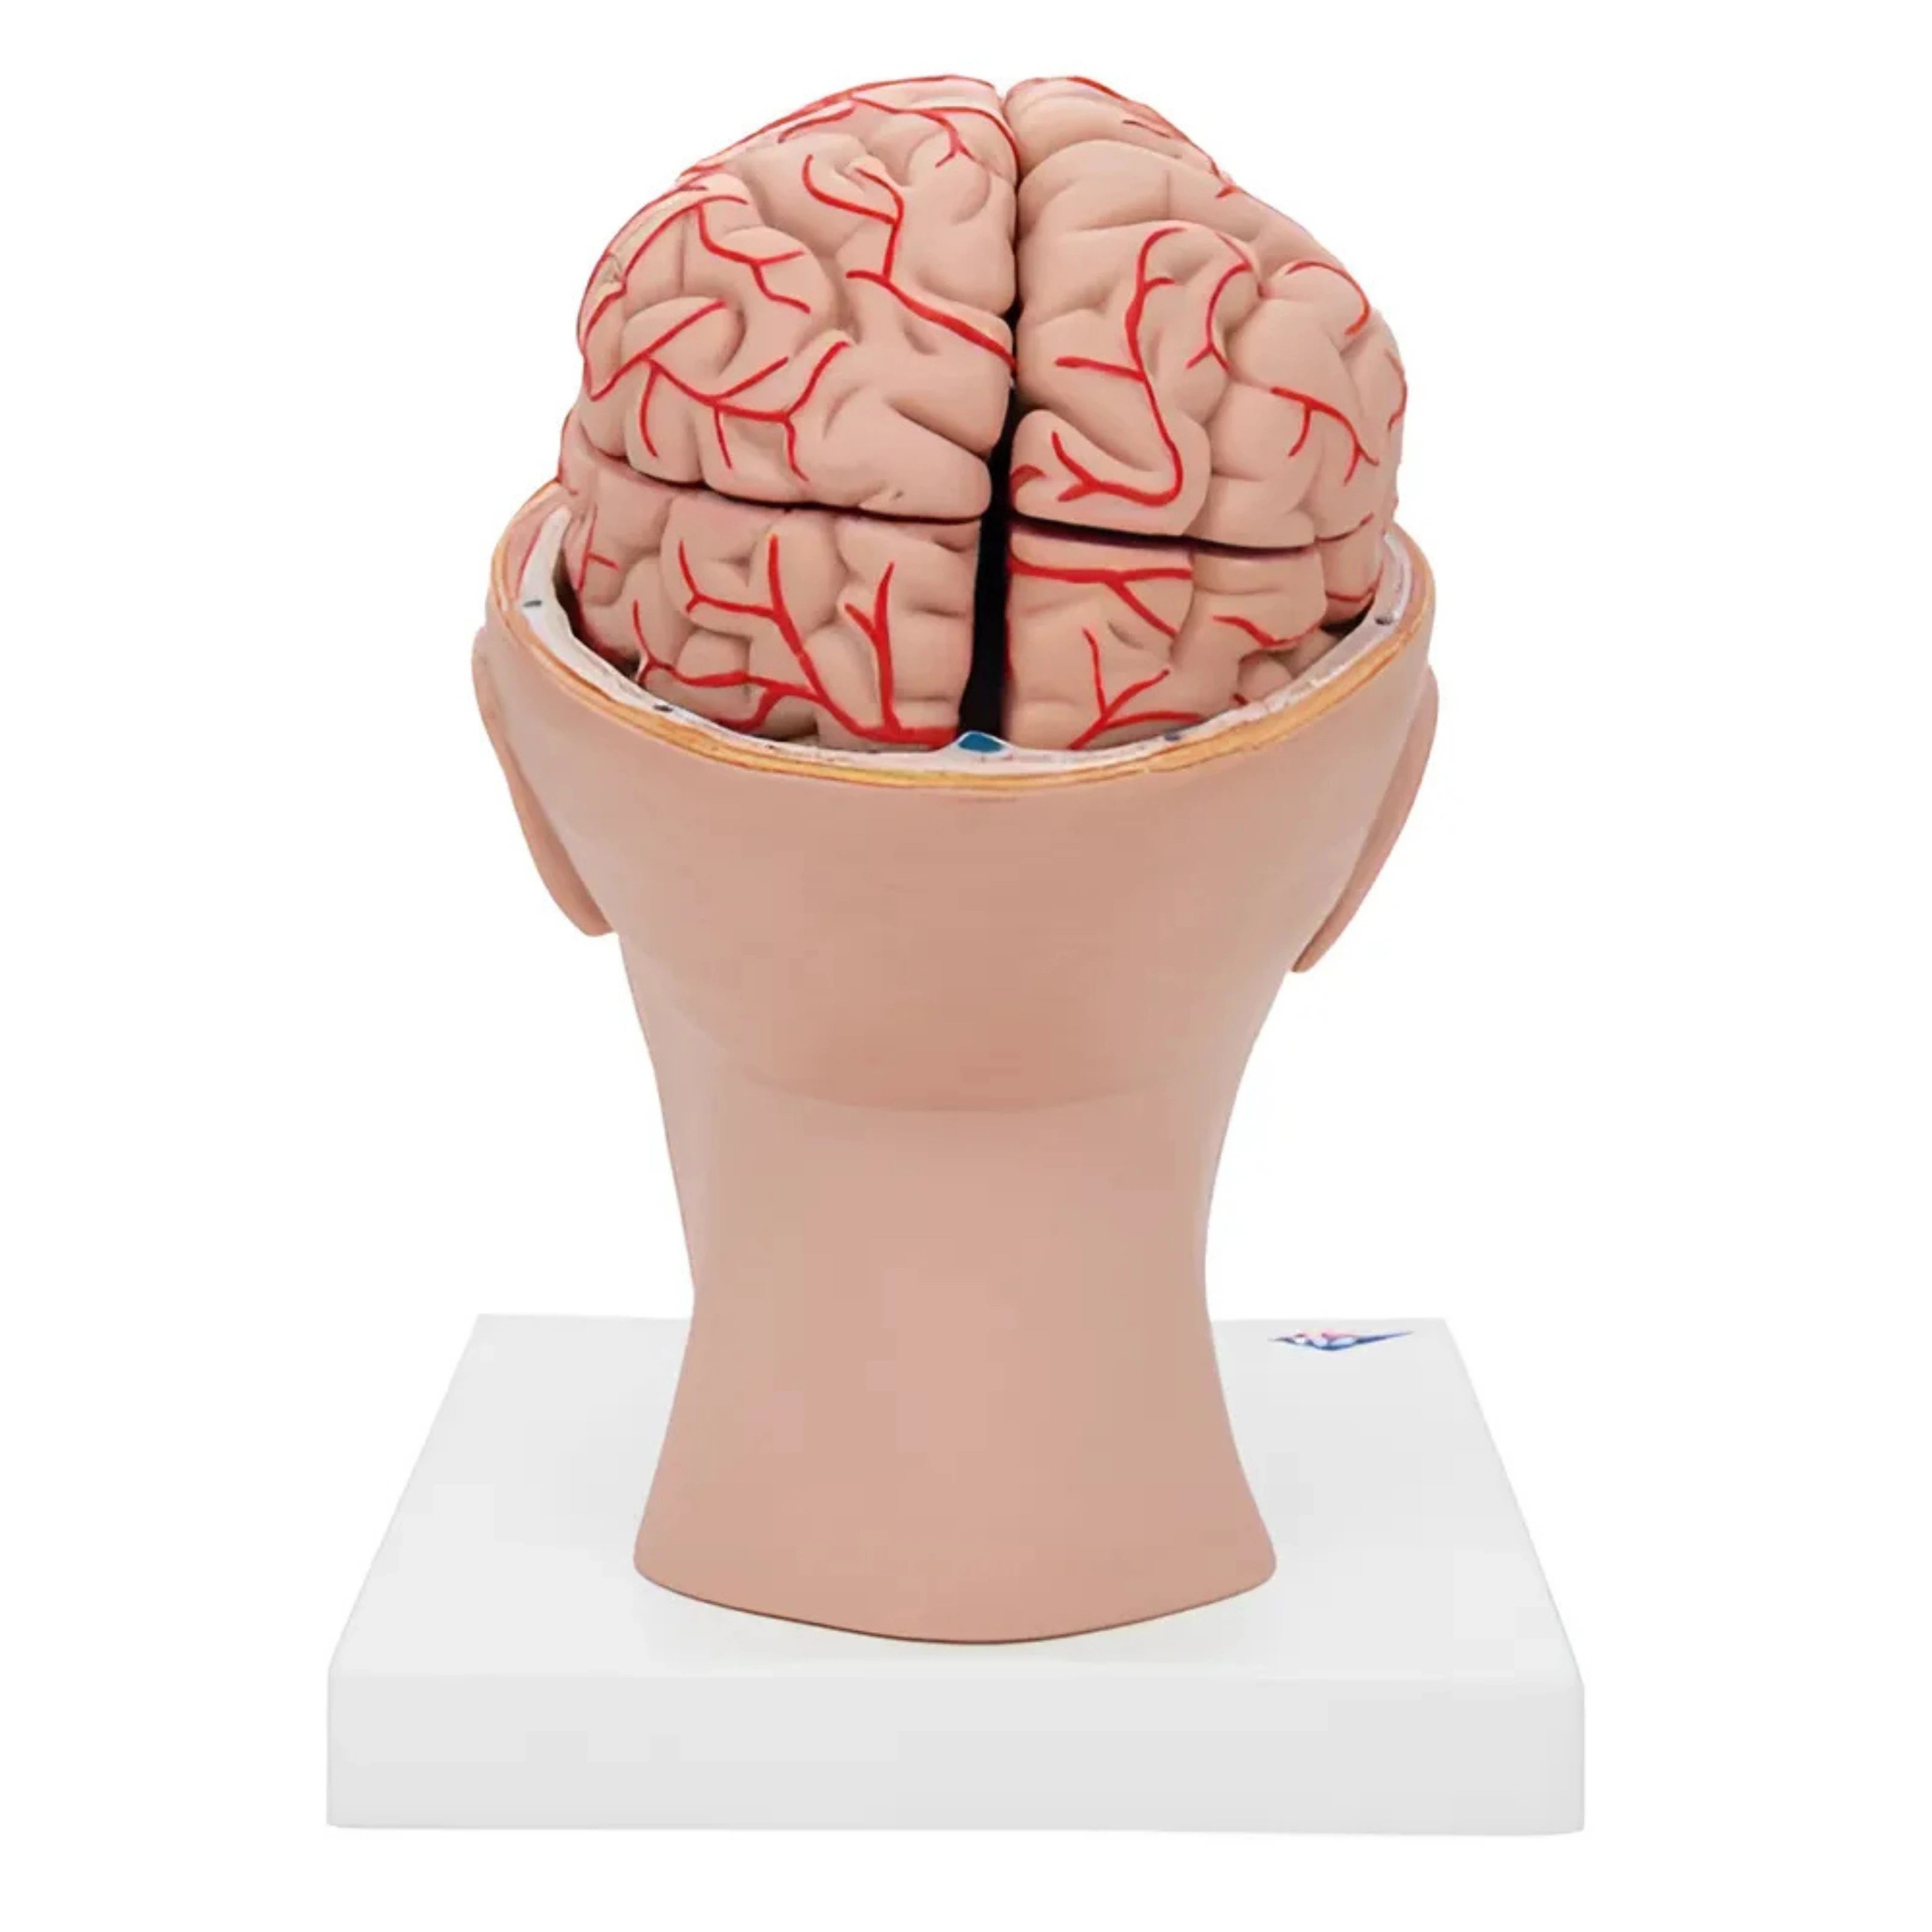

3B Scientific

Encéfalo de lujo con arterias en la base de la cabeza, desmontable en 8 piezas

Precio de venta$22,344.58